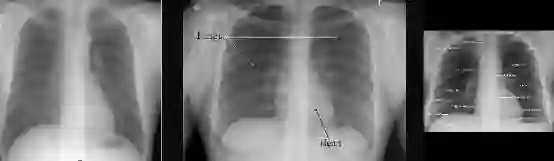

医学成像中,数据存储档案是基于临床假设的。不幸的是,这意味着当你想要提取一个图像时,比如一个正面的胸部x光片,你通常会获得一个存储了许多其他图像的文件夹,并且没有简单的方法来对它们加以区分。

图1:这些图片来自于相同的文件夹是有道理的,因为在放射学中我们记录的是病例而非图像。这是病人受伤后,同时扫描的所有身体部位。

图2:这里只有中间的图像有经典的“黑色边框”